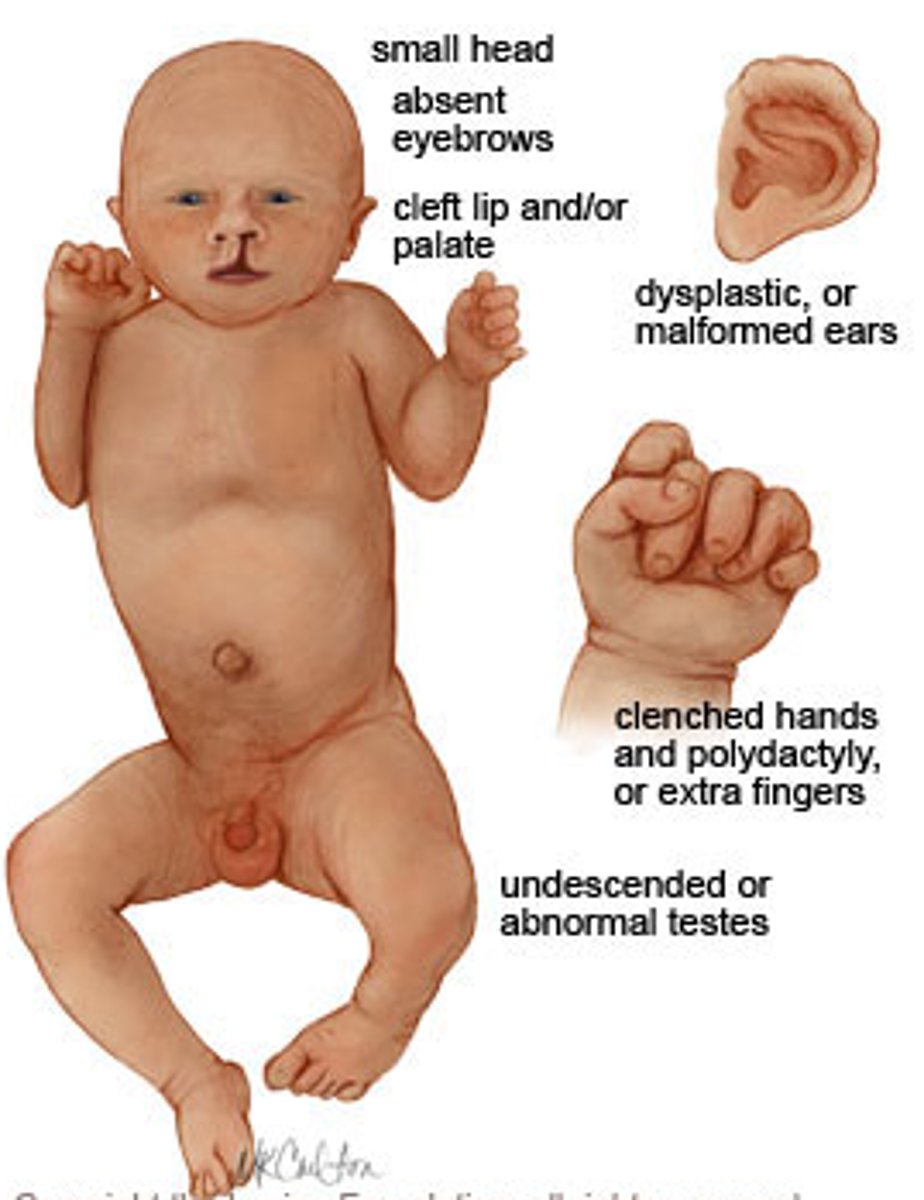

Infant with cleft lip/palate, microcephaly or holoprosencephaly (1 hemisphere), polydactyly, cutis aplasia

Patau syndrome (Trisomy 13)

Mnemonic: P=puberty at 13